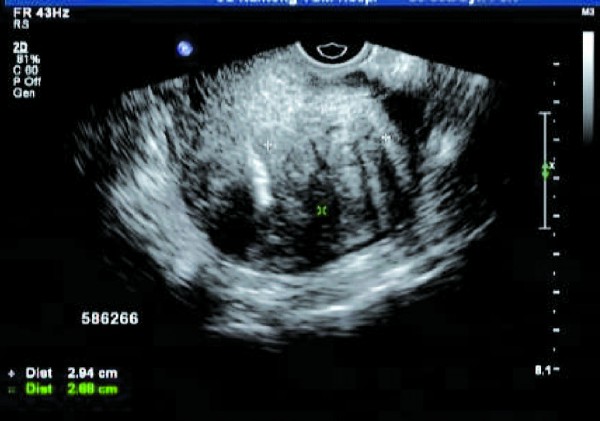

患者,女,47岁。常规体检,B超报告显示: 子宫体前位,大小: 4.63cm×3.97cm×3.78cm,宫颈长:2.56cm。宫壁回声不均匀,肌层回声呈粗颗粒状,外形平滑,后壁厚度2倍于前壁,内膜带状,规则,均质。双卵巢均可探及正常大小,位置正常,未见异常血流信号及频谱。宫旁未见明显占位,直肠窝无暗区。

超声提示:子宫后壁腺肌症

即子宫腺肌瘤,呈边界不清的团块状回声,呈不均质高回声,病灶与正常肌层间没有清晰的边界,即无包膜回声;彩色血流信号丰富,病灶周围无环状彩色血流信号。

经阴道彩色多普勒超声能清晰显示子宫肌层病变的大小、部位、范围,而且能清晰显示其内部结构变化。超声检查时重点观察子宫肌层病灶回声、病灶周边无包膜及病灶内小片状血流信号等特征性表现,能提高诊断符合率。